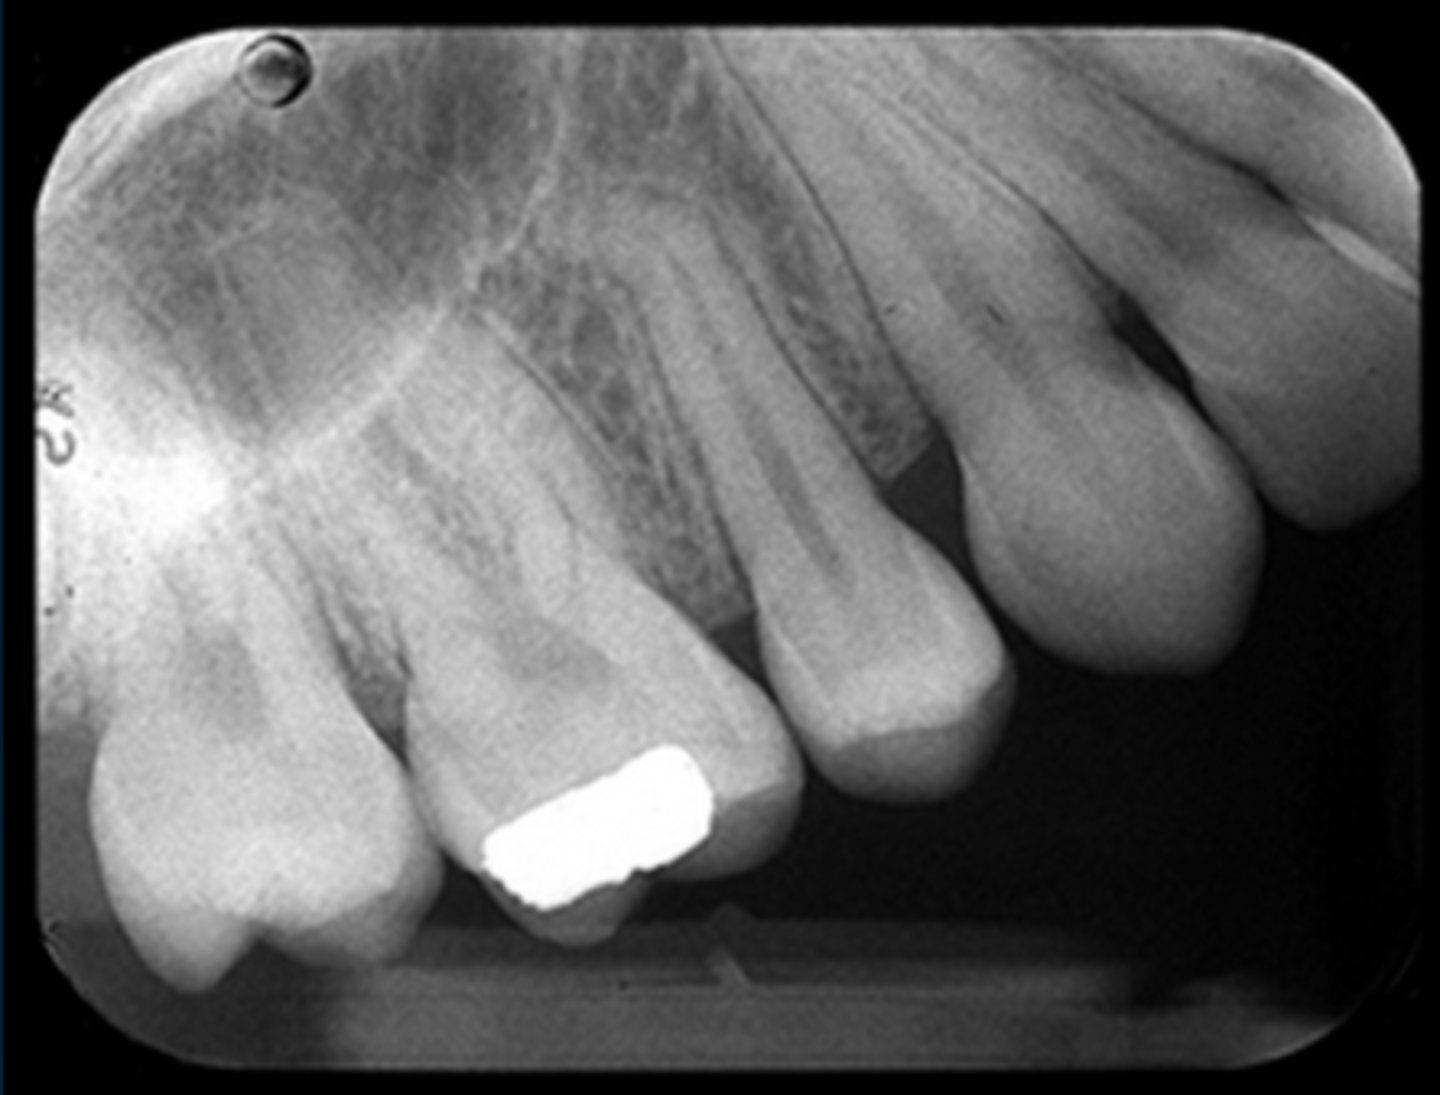

periapical film

shows the entire tooth or teeth and surrounding tissues